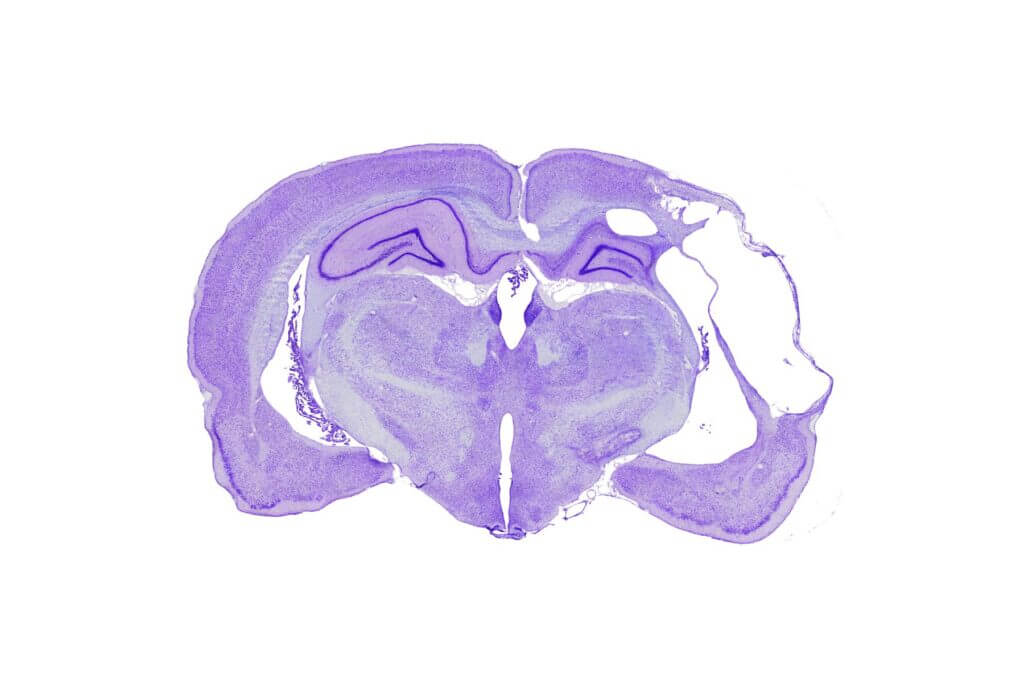

Immunohistochemistry, Immunofluorescence, and Histology